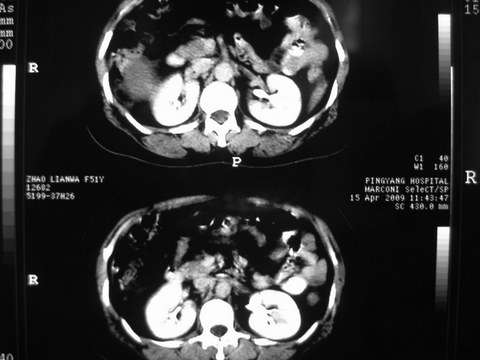

患者 女 51岁 两天前感觉上腹疼,无明显诱因,b超示肝右叶囊实性占位,边缘清楚,其内回声不均匀,ct增强如图,大家看看是什么 ,病人一年前及两月前b超检查只是提示胆囊炎

外院术后,证实肝癌合并出血

特点:1,病灶发展迅速,(2月前正常)[br] 2,囊实性,且并边界清晰光滑,呈右后叶赘生性。囊性区无强化,实性部分较多轻度强化,边界欠清。考虑囊腺癌或囊腺瘤。

出病理 中分化肝细胞癌合并出血